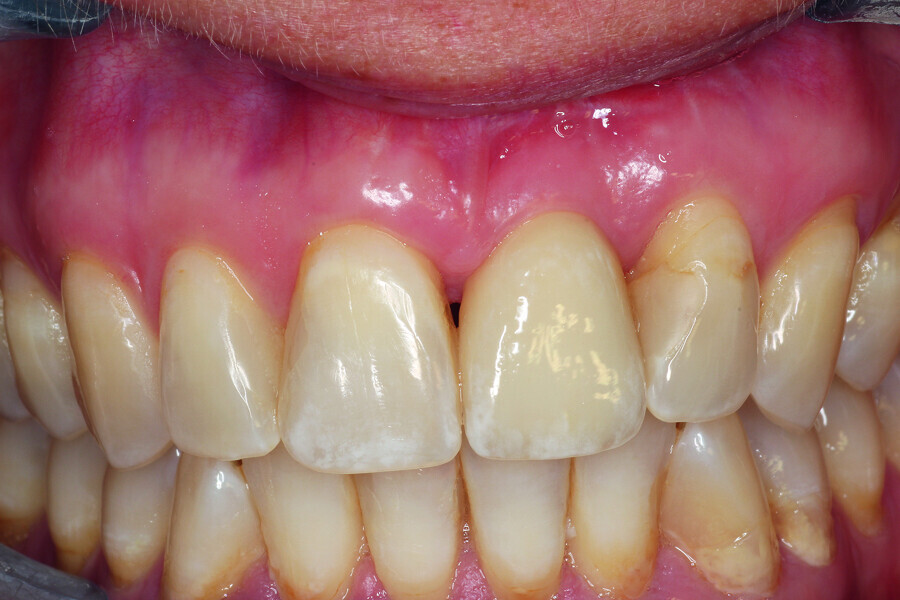

Fig. 4: The implant site was uncovered after five months.